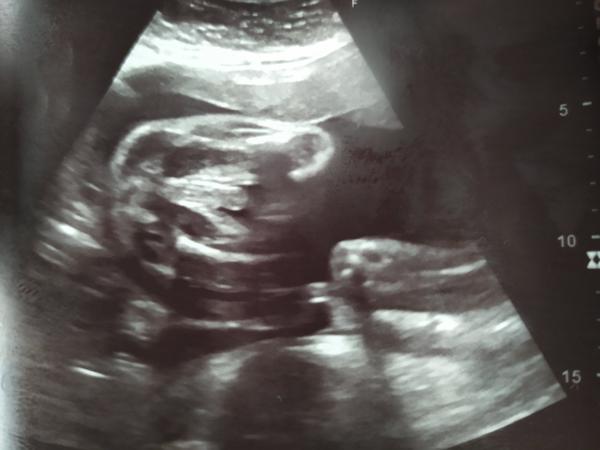

@janagranada na prvním screeningu nebylo vidět vůbec a na druhém to nebylo stoprocentní, fotka co jsem přidávala že z 26tt focena na běžné těhu kontrole, kde Mudr tvrdí kluk, ale mě prostě mate ta fotka no😄 jde tam vidět prostě obojí 😄🤭

Holky, co myslíte? Kluk nebo holka? Když si odmyslím bambulku tak vidím kávové zrno. Vidíte ho taky?

Je možné aby byla bambulka pupečník nebo je to kluk jak buk? 🙂)